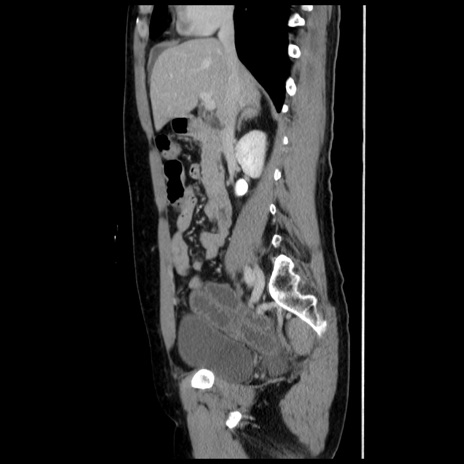

冠状断像

【症例】 50歳代女性

【主訴】 腹痛

【現病歴】前日生レバーを食べた。今朝に排便あり。 昼前に突然発症の腹痛を生じ、当院救急外来を受診した。

【既往歴】 子宮筋腫にてで子宮全摘後

【身体所見】 意識清明、腹部:平坦、軟、下腹部やや左を中心に圧痛・反跳痛あり、筋性防御あり

【データ】WBC 7800、CRP 0.07